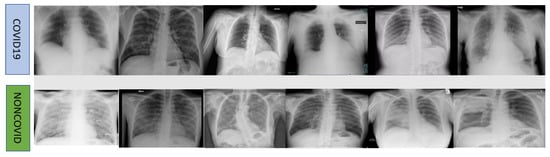

2. Dataset and Methodology